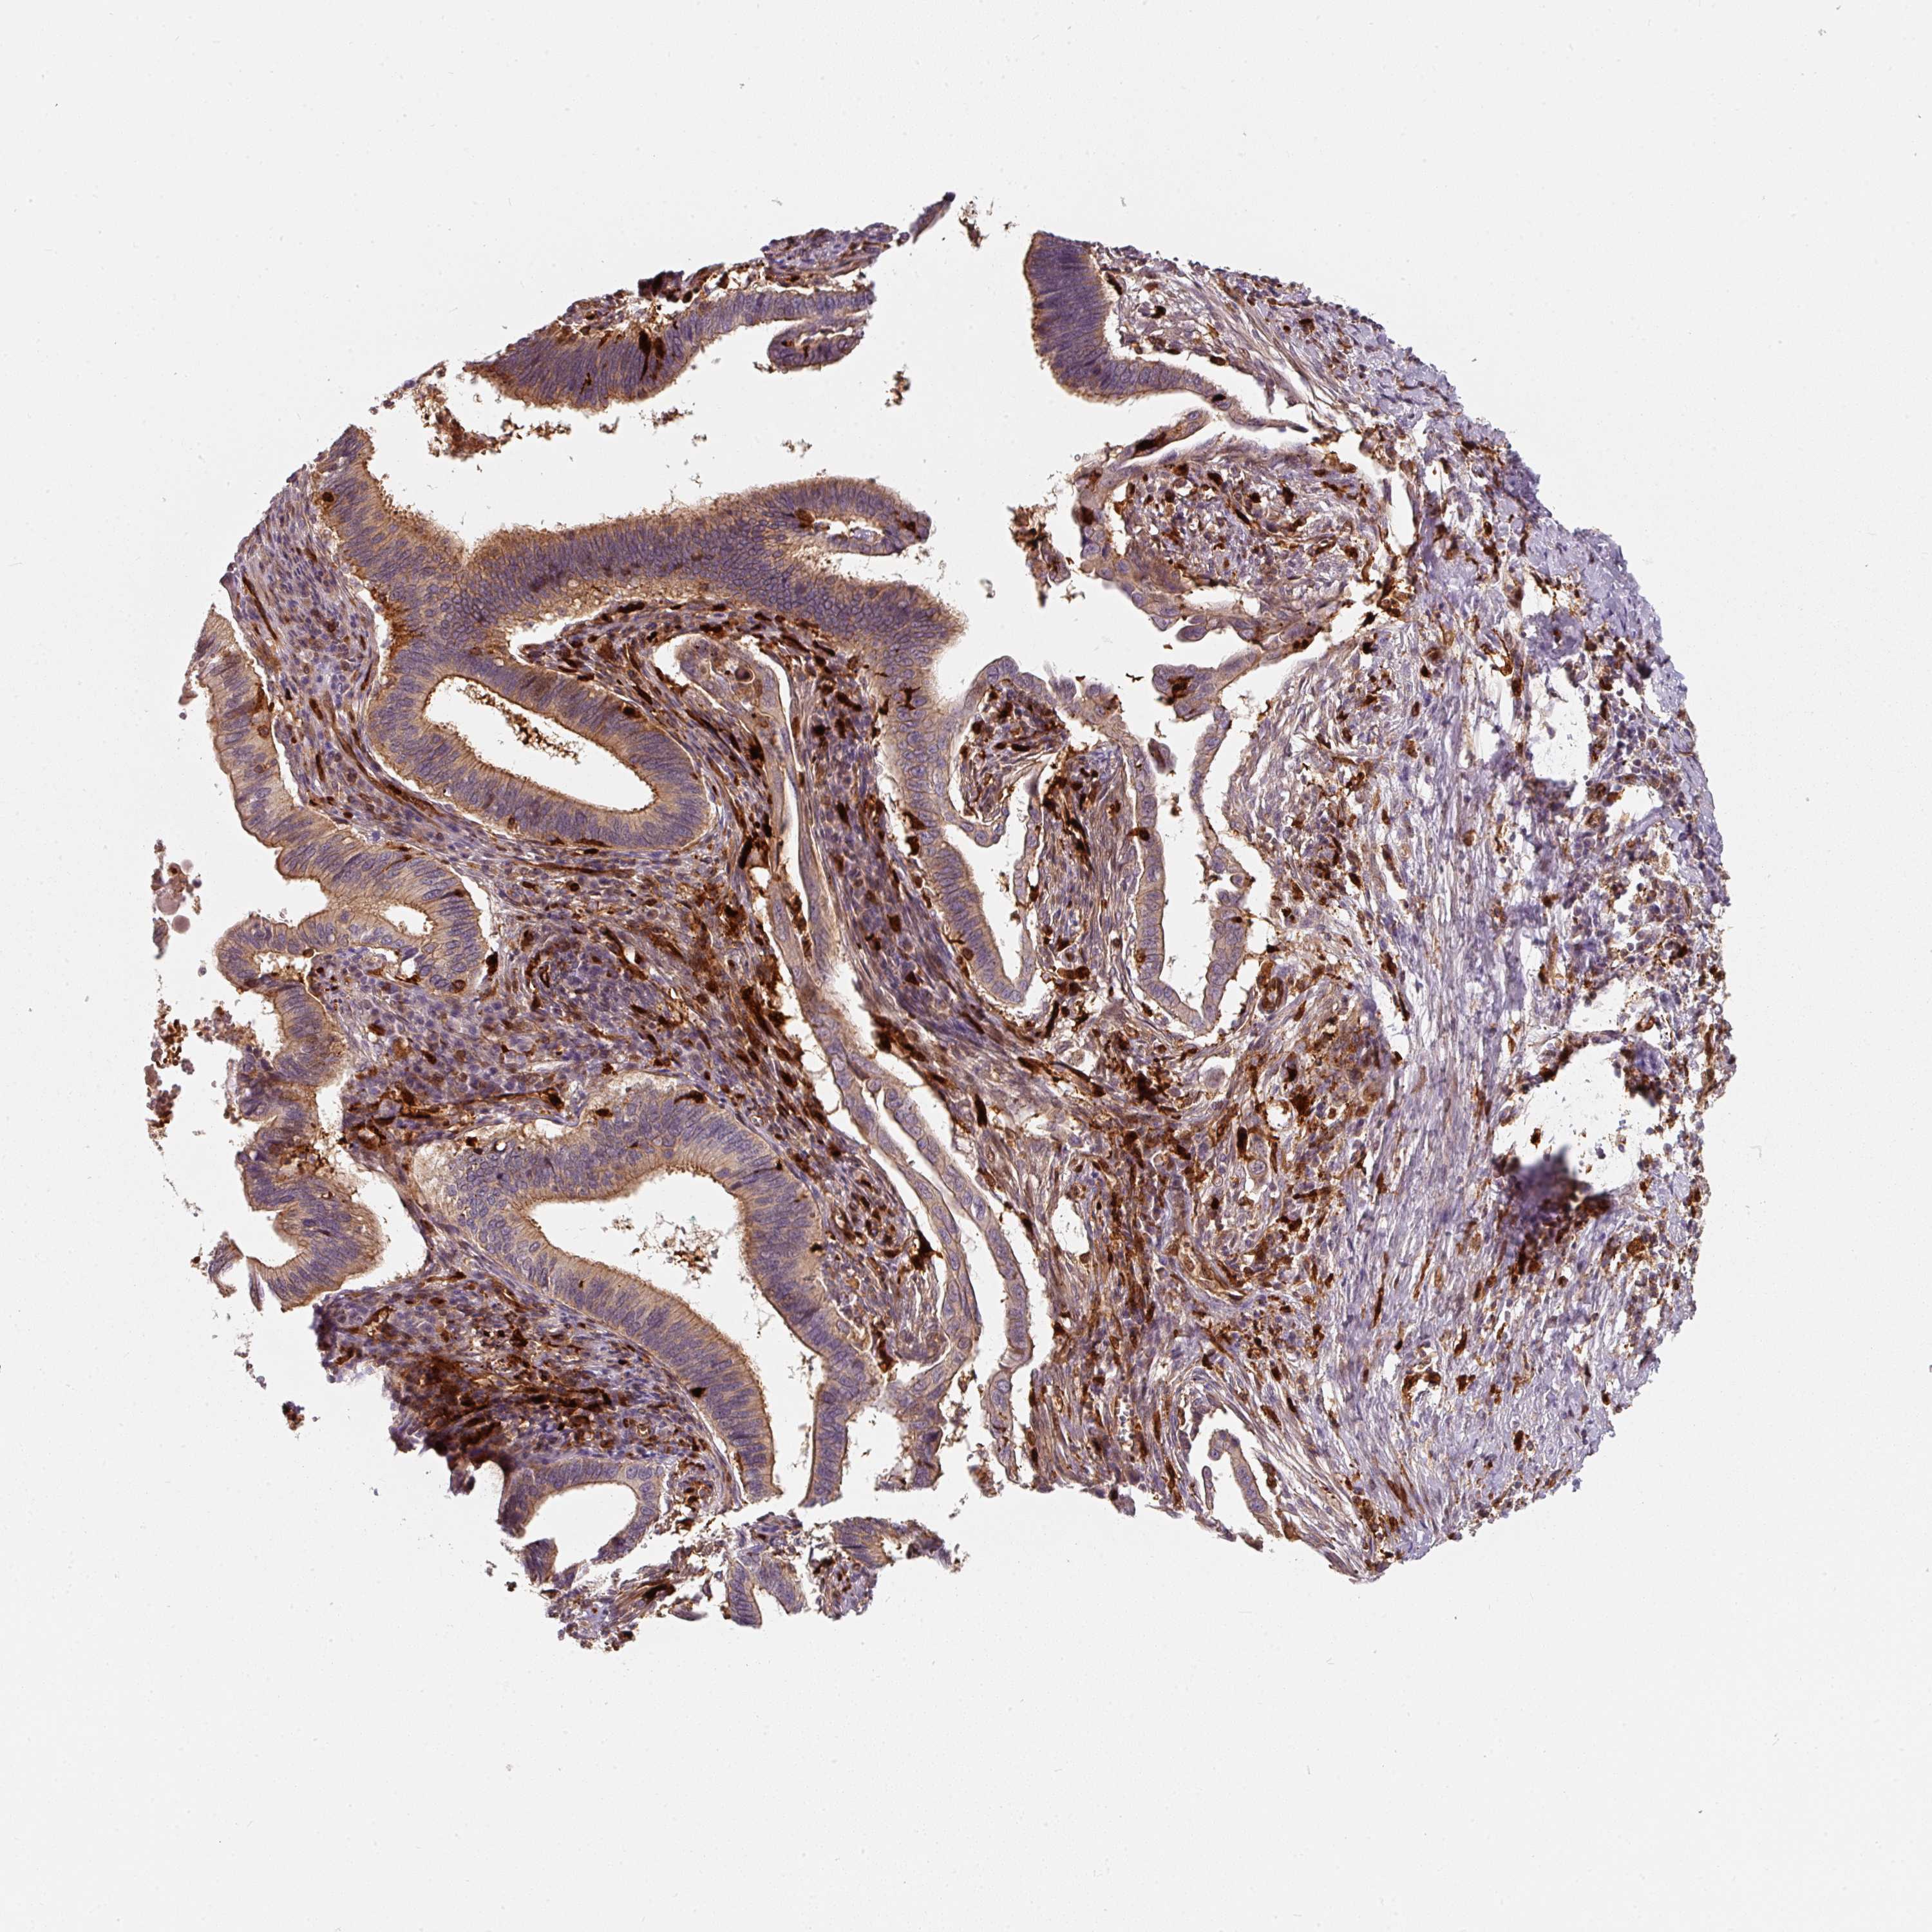

CERVICAL CANCER - Protein expressioni

A mouse-over function shows sample information and annotation data. Click on an image to view it in a full screen mode. Samples can be filtered based on level of antibody staining by selecting one or several of the following categories: high, medium, low and not detected. The assay and annotation is described here.

Note that samples used for immunohistochemistry by the Human Protein Atlas do not correspond to samples in the TCGA dataset.

Antibody stainingi

Antibody staining in the annotated cell types in the current human tissue is reported as not detected, low, medium, or high, based on conventional immunohistochemistry profiling in selected tissues. This score is based on the combination of the staining intensity and fraction of stained cells.

Each image is clickable and will lead to virtual microscopy that enables deeper exploration of all samples and also displays staining intensity scores, fraction scores and subcellular localization as well as patient and tissue information for each sample.

Antibody HPA037403

Antibody HPA037404

Antibody CAB004241

Squamous cell carcinoma, NOS

Adenocarcinoma, NOS